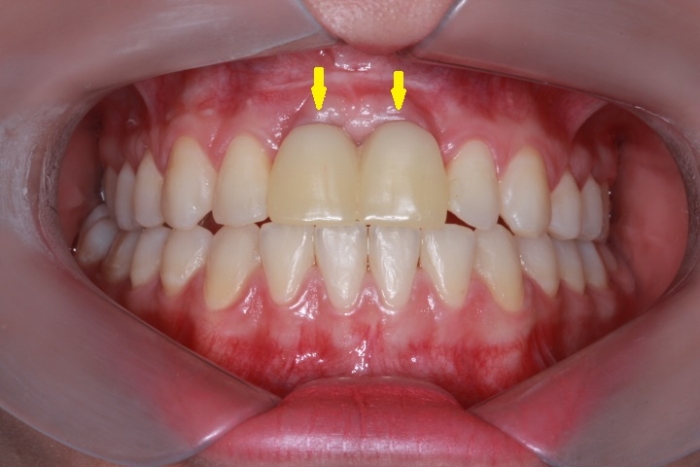

Imagem Inicial 2014